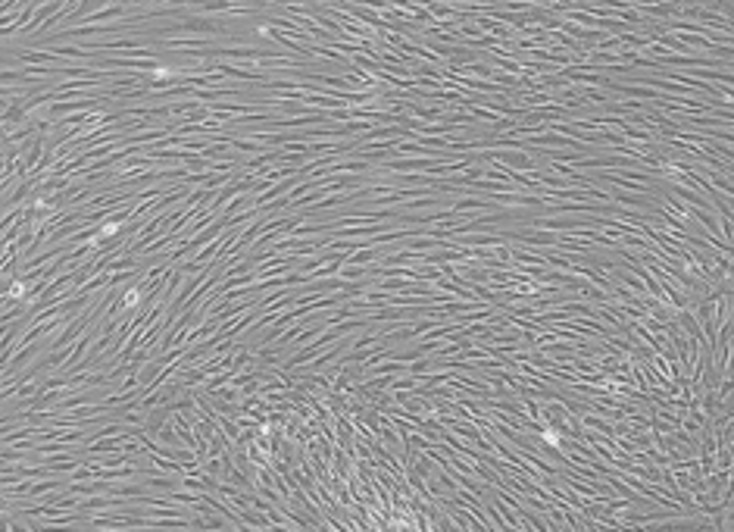

Bone Marrow Mesenchymal Stem Cells (BMSCs) are an important type of adult stem cell found in bone marrow, aside from hematopoietic stem cells. They participate in the formation of the hematopoietic microenvironment and possess characteristics such as multipotent differentiation potential, low immunogenicity, ease of isolation, rapid expansion, and a stable genetic profile. These features provide BMSCs with broad application prospects in tissue engineering, cell therapy, and gene therapy.